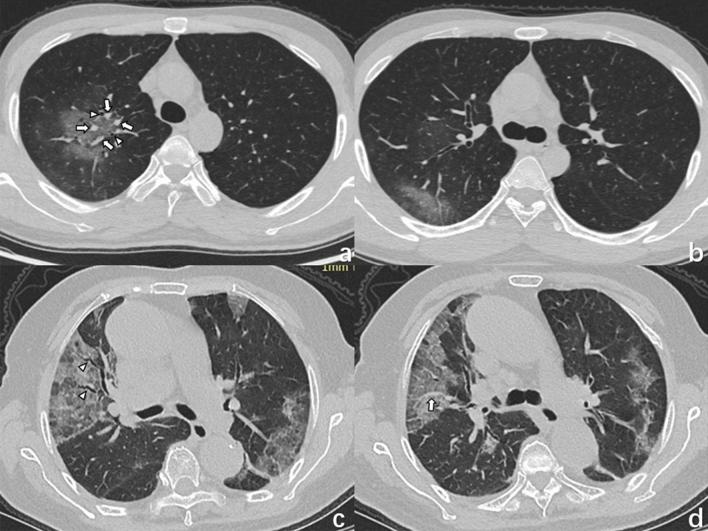

Coronavirus disease 2019 (COVID-19) has spread in more than 100 countries and regions around the world, raising grave global concerns. COVID-19 has a similar pattern of infection, clinical symptoms, and chest imaging findings to influenza pneumonia. In this retrospective study, we analysed clinical and chest CT data of 24 patients with COVID-19 and 79 patients with influenza pneumonia. Univariate analysis demonstrated that the temperature, systolic pressure, cough and sputum production could distinguish COVID-19 from influenza pneumonia. The diagnostic sensitivity and specificity for the clinical features are 0.783 and 0.747, and the AUC value is 0.819. Univariate analysis demonstrates that nine CT features, central-peripheral distribution, superior-inferior distribution, anterior-posterior distribution, patches of GGO, GGO nodule, vascular enlargement in GGO, air bronchogram, bronchiectasis within focus, interlobular septal thickening, could distinguish COVID-19 from influenza pneumonia. The diagnostic sensitivity and specificity for the CT features are 0.750 and 0.962, and the AUC value is 0.927. Finally, a multivariate logistic regression model combined the variables from the clinical variables and CT features models was made. The combined model contained six features: systolic blood pressure, sputum production, vascular enlargement in the GGO, GGO nodule, central-peripheral distribution and bronchiectasis within focus. The diagnostic sensitivity and specificity for the combined features are 0.87 and 0.96, and the AUC value is 0.961. In conclusion, some CT features or clinical variables can differentiate COVID-19 from influenza pneumonia. Moreover, CT features combined with clinical variables had higher diagnostic performance.

2019冠状病毒病(COVID-19)已在全球100多个国家和地区传播,引起了全球的严重关注。COVID-19在感染模式、临床症状和胸部影像学表现方面与流感肺炎相似。在这项回顾性研究中,我们分析了24例COVID-19患者和79例流感肺炎患者的临床及胸部CT数据。单因素分析表明,体温、收缩压、咳嗽和咳痰情况可将COVID-19与流感肺炎区分开来。临床特征的诊断敏感性和特异性分别为0.783和0.747,AUC值为0.819。单因素分析表明,9个CT特征,即中央-外周分布、上下分布、前后分布、磨玻璃影(GGO)斑片、GGO结节、GGO内血管增粗、空气支气管征、病灶内支气管扩张、小叶间隔增厚,可将COVID-19与流感肺炎区分开来。CT特征的诊断敏感性和特异性分别为0.750和0.962,AUC值为0.927。最后,构建了一个多因素逻辑回归模型,该模型结合了临床变量模型和CT特征模型中的变量。联合模型包含6个特征:收缩压、咳痰、GGO内血管增粗、GGO结节、中央-外周分布和病灶内支气管扩张。联合特征的诊断敏感性和特异性分别为0.87和0.96,AUC值为0.961。总之,一些CT特征或临床变量可将COVID-19与流感肺炎区分开来。此外,CT特征与临床变量相结合具有更高的诊断效能。